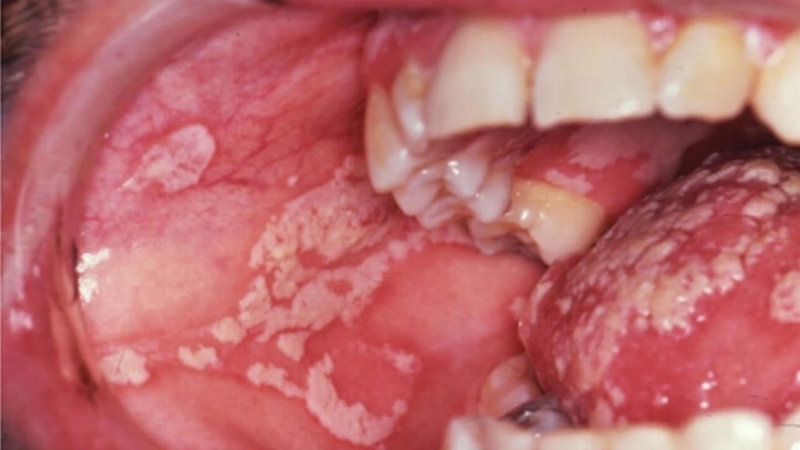

• Nhiều đốm, giả mạc: Quan sát mắt thường có thể thấy nhiều đốm, nốt giả mạc màu trắng hoặc vàng như sữa, xốp, mủn, dễ bong, có thể kèm phù nề, đỏ niêm mạc miệng. Đặc biệt thường biểu hiện nặng nề ở trẻ nhỏ, người già và phụ nữ đang cho con bú.

Nấm miệng là giai đoạn nào của HIV?

Một số nghiên cứu chỉ ra rằng nấm miệng có thể là triệu chứng đầu tiên giúp phát hiện bệnh HIV ở người bình thường, tìm ra một cách tình cờ hoặc khi đã có triệu chứng rõ ràng, phần lớn bắt đầu từ giai đoạn 2 của HIV. Đây cũng là một dấu hiệu cảnh báo bạn có nguy cơ bị nhiễm trùng nặng hơn do hệ miễn dịch bị suy giảm nặng nề bởi virus HIV.

Nấm Candida là tác nhân chủ yếu, có tới 80-90% bệnh nhân HIV bị nhiễm nấm miệng. Khi HIV tiến triển xâm nhập vào hệ miễn dịch của con người, nguy cơ phát triển nấm miệng cũng tăng lên. Các bệnh mắc phải khác có thể gặp bên cạnh nấm đó là: Lao, nhiễm trùng nặng do vi khuẩn (viêm phổi, viêm mủ màng phổi, viêm màng não, nhiễm khuẩn huyết, nhiễm trùng xương khớp,...), thiếu máu kéo dài,...